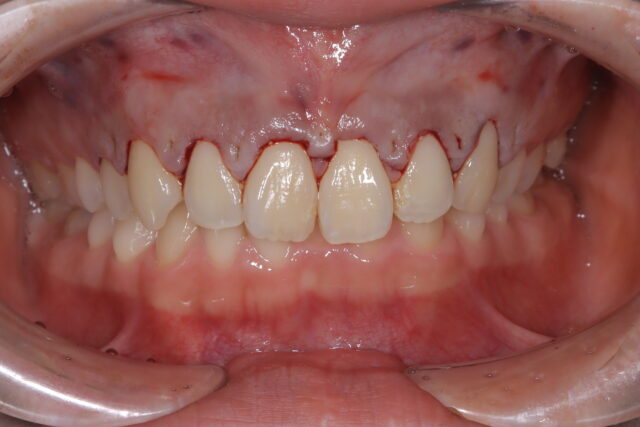

After

歯冠長延長術、直後の状態

2時間でガミースマイルが改善しました。

本町ノーブル歯科 矯正歯科オリジナル『見えない縫合』でオペ直後から綺麗!!

最小限の歯茎の剥離と超音波での施術でオペ後のダウンタイムを最小限にします。

歯冠長延長術2週間後の状態

痛みなくほぼダウンタイムはありません!

歯ぐきもほとんど治っています。(今回の症例は笑っても唇を上がらなくするリップリポジショニングも適応症でしたが患者様が満足されたのでここで治療は終了しました。)切開線、極細糸、縫合方法、超音波にこだわる事で2週間で治癒します。

(他院の症例は多くがオペ後1ヶ月以上経った写真です。)ガミースマイル治療Before After

2.0mmであなたの笑顔は大きく変わります!!

上記の患者様は歯冠長延長術(クラウンレングスニング)で治療しました。

治療期間:2週間(施術時間は2時間)

費用:16.5万〜23.1万円

デメリット、注意点:出血、腫脹、疼痛、内出血の可能性がある矯正をした後ガミースマイルで10年間ずっと悩んでいたけど治療した症例はコチラ